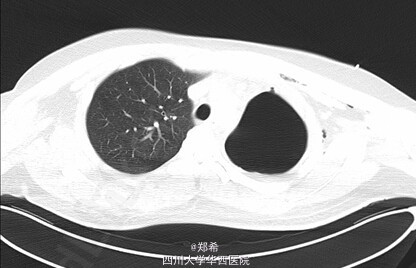

查体:左肺呼吸音低。胸部增强CT示:左肺上叶舌段实变肺不张,左主支气管内见高密度支架影,支架内可见少许软组织密度影,其远端左主支气管管壁稍厚,多系炎症;左肺门淋巴结增大;心包少量积液;左侧胸膜增厚,左侧胸腔少量积液。

初步诊断:1、左主支气管狭窄2、左主支气管支架置入术后3、支气管内膜结核.全麻下行左主支气管支架取出+左全肺切除术。术中见: 左主支气管与周围组织粘连较重,切开后见官腔内支架扭曲,陷入支气管壁,肉芽组织增生明显。手术顺利,术后入ICU继续治疗。